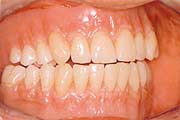

Der Natur am nächsten ist es, die naturgegebene Situation wieder herzustellen: Mit einer Implantatkrone wird die sichtbare Zahnkrone und die unsichtbare Zahnwurzel ersetzt - so, als wäre es Ihr eigener Zahn. Sichern Sie sich langfristig ein Höchstmaß an sicherem Auftreten und Komfort!

Was sind Zahnimplantate?

Zahnimplantate ersetzen die fehlenden Zähne einschließlich

der Zahnwurzel und werden an deren Stelle in den Kieferknochen eingesetzt.

Diese lohnende und sichere Alternative ist in der modernen Zahnheilkunde

längst anerkannt und hat sich erfolgreich durchgesetzt.

Die Erfahrungen reichen weit über 30 Jahren zurück und beruhen weltweit auf fundierten Erkenntnissen. Durch das spezielle Design des von uns verwendeten CAMLOG(r)-Systems gewinnt Ihr Zahnersatz höchste Stabilität und Ästhetik. Für Sie eine große Sicherheit im Alltag!

Implantate bestehen aus Titan, und werden daher sehr körperfreundlich angenommen. Sie lösen keine allergischen Reaktionen aus. Durch eine natürliche Belastung der Knochenzellen verhindert das Implantat nach dem Zahnverlust einen Knochenabbau und damit auch Zahnfleischschwund. Dieses ist kosmetisch sehr vorteilhaft. Der Komfort und die Langlebigkeit von Zahnersatz auf Implantaten können gegenüber herkömmlicher Methoden oft entscheidend verbessert werden.